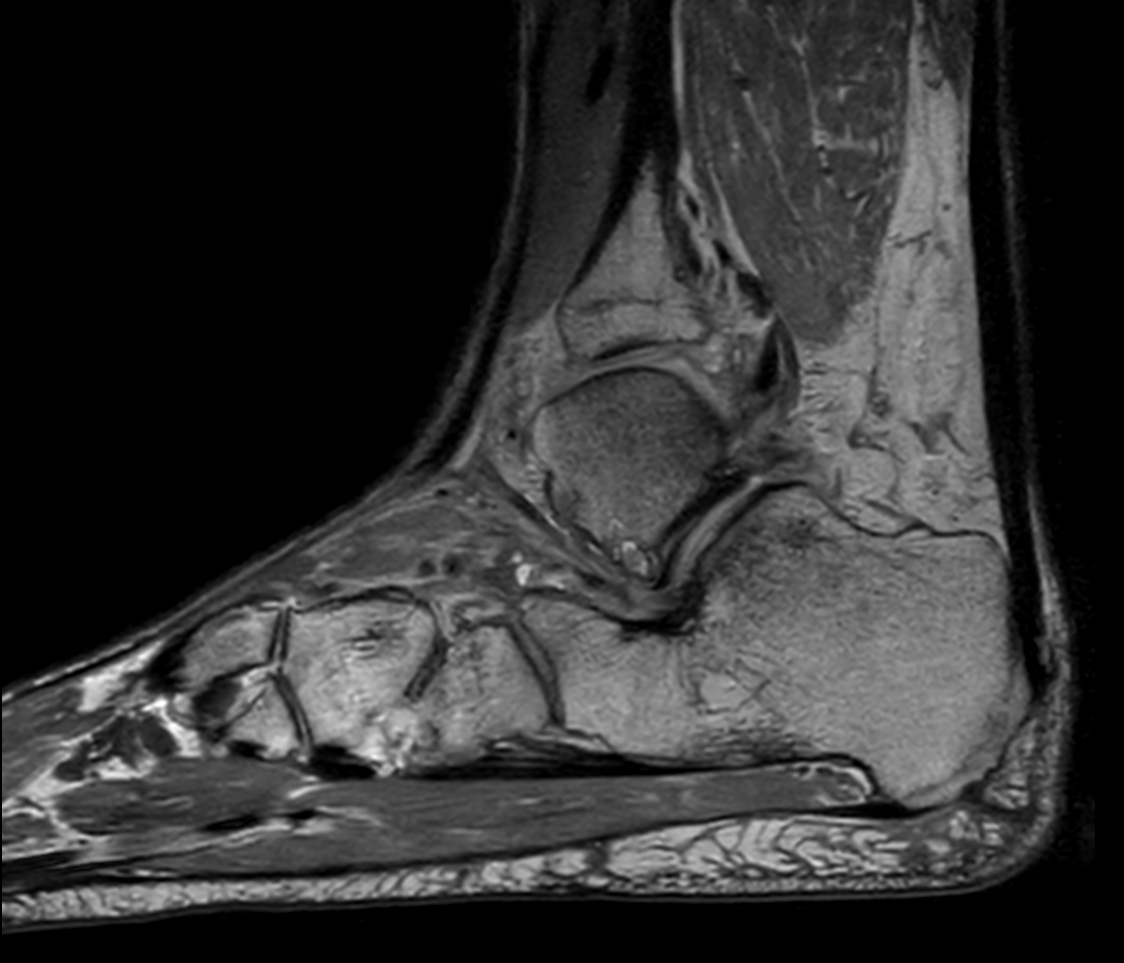

Sagittal PDw TSE mDIXON XD (In Phase)

Sagittal PDw TSE mDIXON XD (Partial FatSat)

Sagittal PDw TSE mDIXON XD (Water only)

Sagittal 3D PDw MSK VIEW